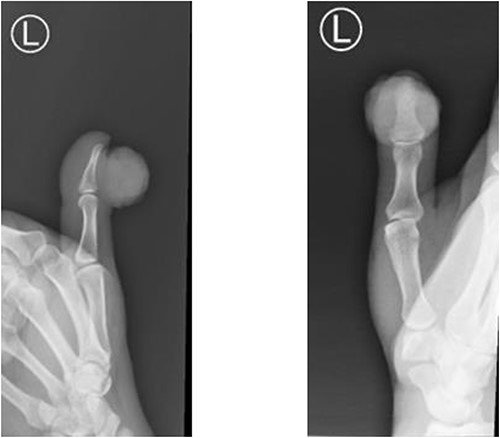

Upon examining the left thumb, an exophytic red, firm, well-circumscribed mass, measuring around 2 × 3 × 4 cm in dimensions, occupied the eponychial fold. The mass had irregular surface with some ulcerations and necrotic tissues (Fig. 1). The mass was not tender, however had the tendency to bleed easily. The thumb interphalangeal joint (IPJ) motions were normal. The left thumb nail plate showed no abnormality apart from the extension of the mass from the eponychial fold to cover almost two-thirds of the nail plate in a frontal view and nearly 50% in a lateral view. There were no other masses or palpable lymph nodes. Examination of the chest and abdomen was unremarkable. All laboratory investigations were within normal values. Hand radiographs revealed a radiopaque soft tissue swelling over the IPJ of the left thumb without bony involvement (Fig. 2). Magnetic resonance imaging of left thumb was conducted and revealed a large hypervascular exophytic lesion of distal thumb, highly suspicious for malignancy, no signs of any bony invasion however the lesion is inseparable from distal fibres of the extensor tendon (Fig. 3). Computed tomography of the chest, abdomen and pelvis was carried out, and revealed multiple enlarged left axillary lymph nodes with no abdominal or pelvic metastasis. Incisional biopsy of the mass reported as extensively ulcerated and necrotic skin, bacterial colonies and tiny foci of capillary proliferation, immunohistochemistry for HHV8 was negative. However, malignancy, namely, squamous cell carcinoma could not be ruled out from this specimen.

Radiopaque soft tissue swelling over the IPJ of the left thumb without bony involvement.